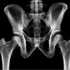

The U.S. Food and Drug Administration said on October 1st 2007 it was reviewing reports of abnormal heartbeats in patients who took medicines in a class of osteoporosis drugs called bisphosphonates. This is just a precaution after a study published in the New England Journal of Medicine last May described increased rates of serious atrial fibrillation, a type of abnormal heartbeat, in patients who took either of two bisphosphonate drugs Fosamax and Reclast. These drugs are normally prescribed to increase bone mass and reduce fracture risk in patients with osteoporosis. They also are used to slow bone turnover in patients with a disorder called Paget’s disease and to treat bone metastases and lower blood calcium in cancer patients. Other commonly prescribed bisphosphonate drugs include Boniva, Actonel, Sanofi-Aventis; Zometa, Aredia; Didronel, and Skelid.